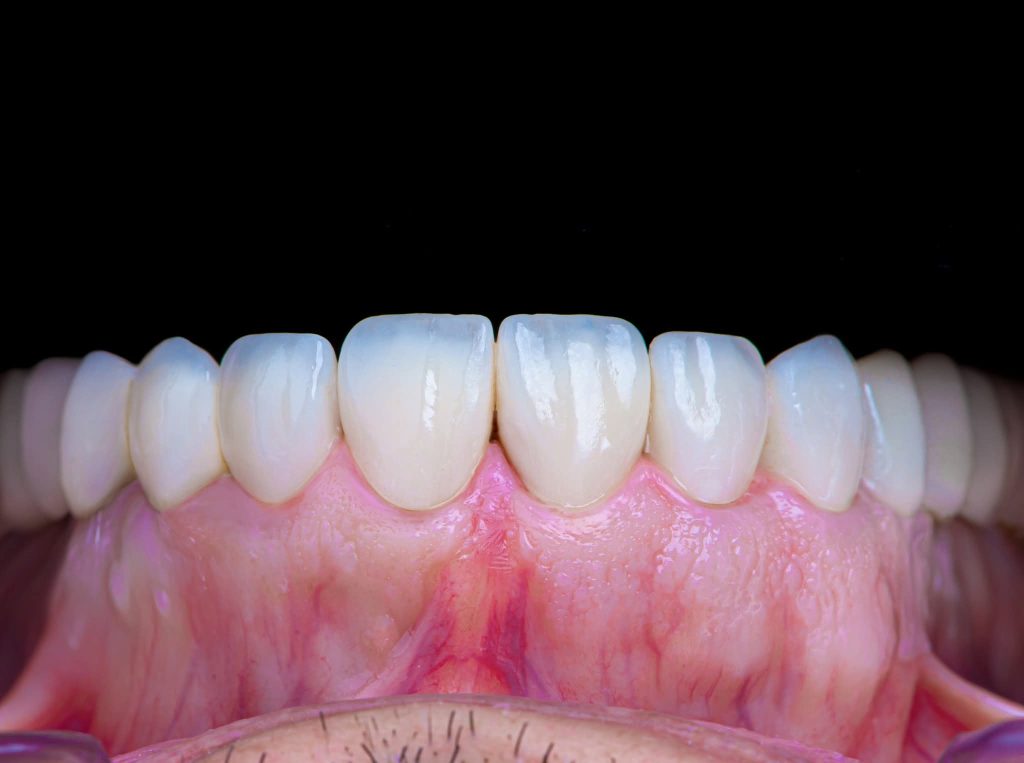

3. Definitive Phase:

This phase began with the upper arch:

Placement of implants in the free-end areas.

Preparation of teeth and insertion of the fixed prosthesis.

The lower arch was managed similarly to the upper arch.

The patient has now been under follow-up for nearly 4 years and remains very happy and comfortable.